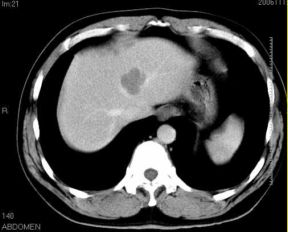

男性,48岁

肝内占位,性质?

肝内多发低密度占位病变,边缘清晰,无强化,肝转移瘤可能

肝内多发低密度占位病变,边缘清晰,无强化,肝转移瘤可能大,请将胃喝水充盈以后再扫描看看,我看大弯侧胃壁较厚。

肝内多发不规则形状低密度灶,强化不明显,考虑转移,积极查找原发灶

肝内多发低密度类圆形病灶,边缘清晰.增强无强化.

意见:1,考虑多发转移瘤;

2,囊肿与血管瘤不排除.

1肝内多发低密度影,考虑:转移瘤 2胃大弯侧胃壁明显增厚,建议胃镜检查除外胃癌